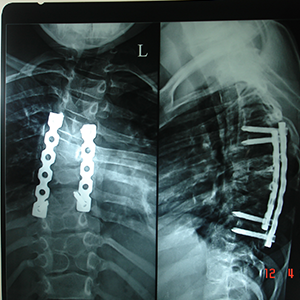

Generally cervical myelopathy with kyphotic cervical slpine is treated with anterior

decompression and fusion.

But this newer technique widely used in japan, allows posterior decompression with

preservations of movement at treated levels